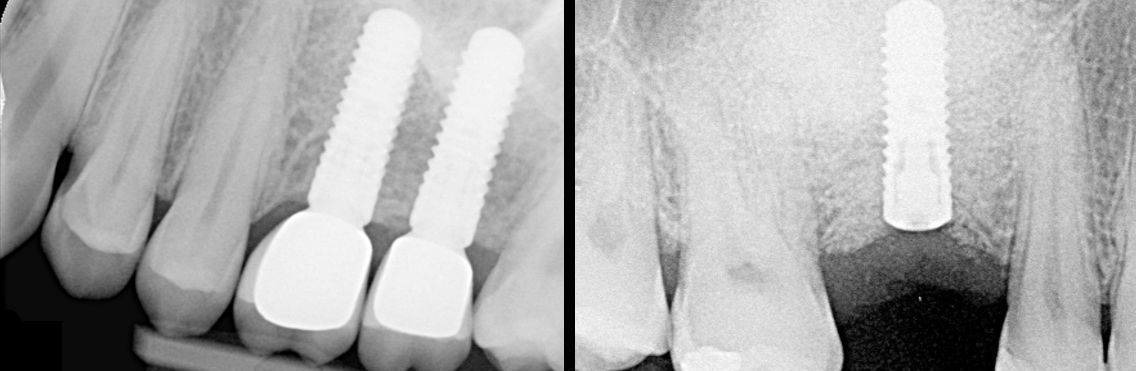

Zahnimplantologie

Rekonstruktion der Kaufähigkeit durch künstliche Zahnwurzeln (Implantate) aus Titan oder Keramik.

Wenn erforderlich, knöcherne Rekonstruktion des „verlorengegangenen“ Kieferknochens, um eine Implantation zu ermöglichen.

- Implantation